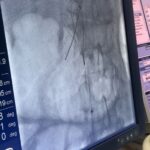

وبسبب الانسداد الكامل في المسار التقليدي، تم تنفيذ TIPS بطريقة معكوسة (Inverted TIPS)، حيث أُدخلت الدعامة عبر الجلد، مروراً بالكبد، لتصل إلى فرع من الوريد البابي، ثم عَبَرت الكبد مجدداً إلى الوريد الأجوف السفلي تحت مستوى الانسداد. وقد أدى هذا الابتكار إلى استعادة تدفق الدم وتخفيف الضغط البابي، مما أنهى النزيف والاستسقاء وساهم في استقرار حالة المريض بشكل كبير.